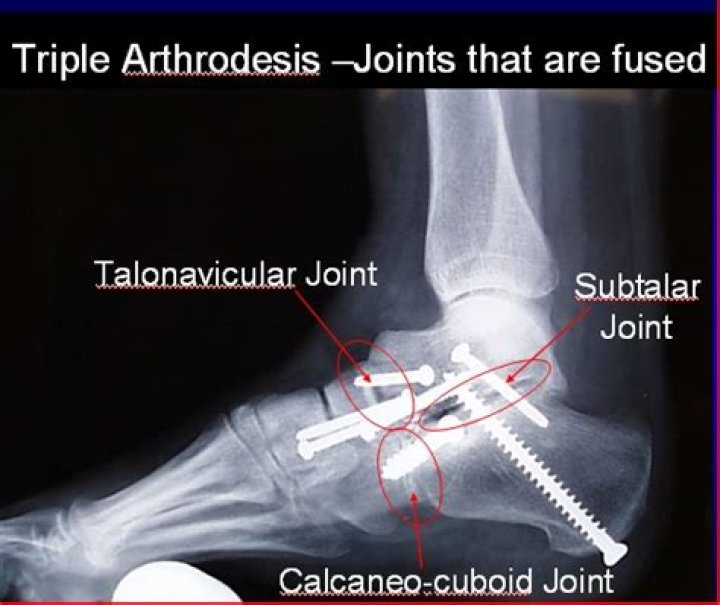

Most triple arthrodesis procedures are performed by removing all of the cartilage from the three joints involved—that is, the talocalcaneal (TC) joint (also referred to as the subtalar joint), the talonavicular (TN) joint, and the calcaneocuboid (CC) joint—and fusing them with bone-to-bone contact.

The term “triple” arthrodesis refers to a fusion procedure of three joints of the hindfoot and midfoot, the subtalar joint (talus and calcaneus), the talonavicular joint, and the calcaneocuboid joint.

What is a triple fusion in a foot and ankle?

A triple arthrodesis is a fusion in the hindfoot (back of the foot) used to treat many types of painful foot deformities. This procedure fuses the joints under the ankle that allow the foot to move from side to side. These joints are the talonavicular, subtalar, and calcaneocuboid.